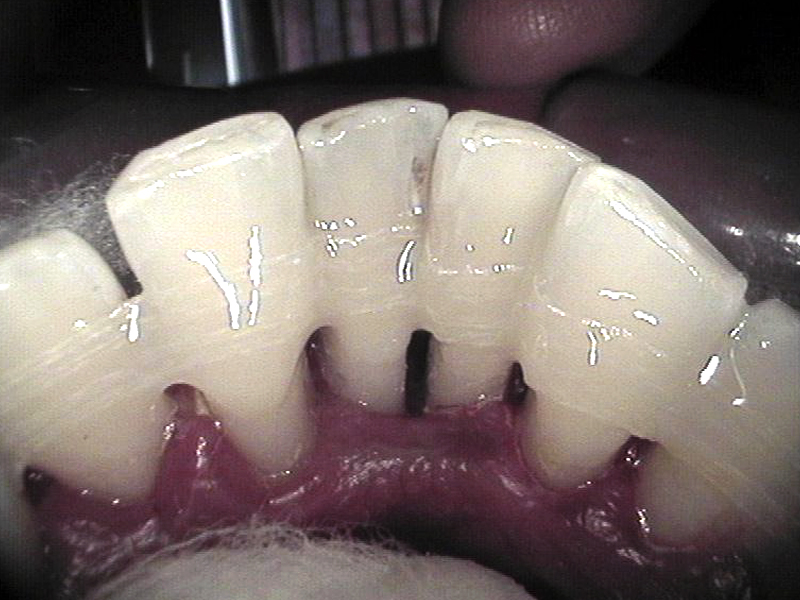

Spilinting